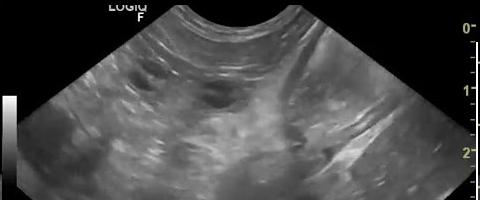

Aspect

echographique de ulcere gastrique est l'epaissisement

hypoechogene de la paroi gastrique localise et parfois un

artefact a interieure du niche . Il se donne de image

nette sur les niches ce qui avait sa taile de passe 2cm de

diametre